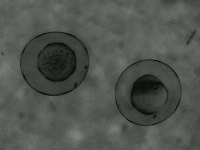

Research & Development: Researchers studying embryo development can use the AliDatabase to automate the process of identifying different stages of zeb1 cells. This can speed up research and reduce the possibility of human error in stage classification.

Medical Diagnosis: In fertility clinics or other medical settings, the AliDatabase can be utilized to identify and sort unfertilized or unhealthy zeb1 cells. This could help in diagnosing certain fertility issues and developing treatment plans.

Educational Tools: The model can be used as an educational tool for biology or medical students. By using AliDatabase, students can better understand the stages of zeb1 cell development and engage with interactive studying methods.

Pharmaceutical Testing: Companies developing drugs or treatments that impact cell growth could use AliDatabase to monitor how zeb1 cells respond at different stages to these drugs, aiding in efficacy and safety tests.

Quality Control in Lab Conditions: The model can be used to identify 'bad' or 'advanced' stages of zeb1 cells, indicating contamination or other issues in lab conditions, thereby assuring the quality of scientific experiments.